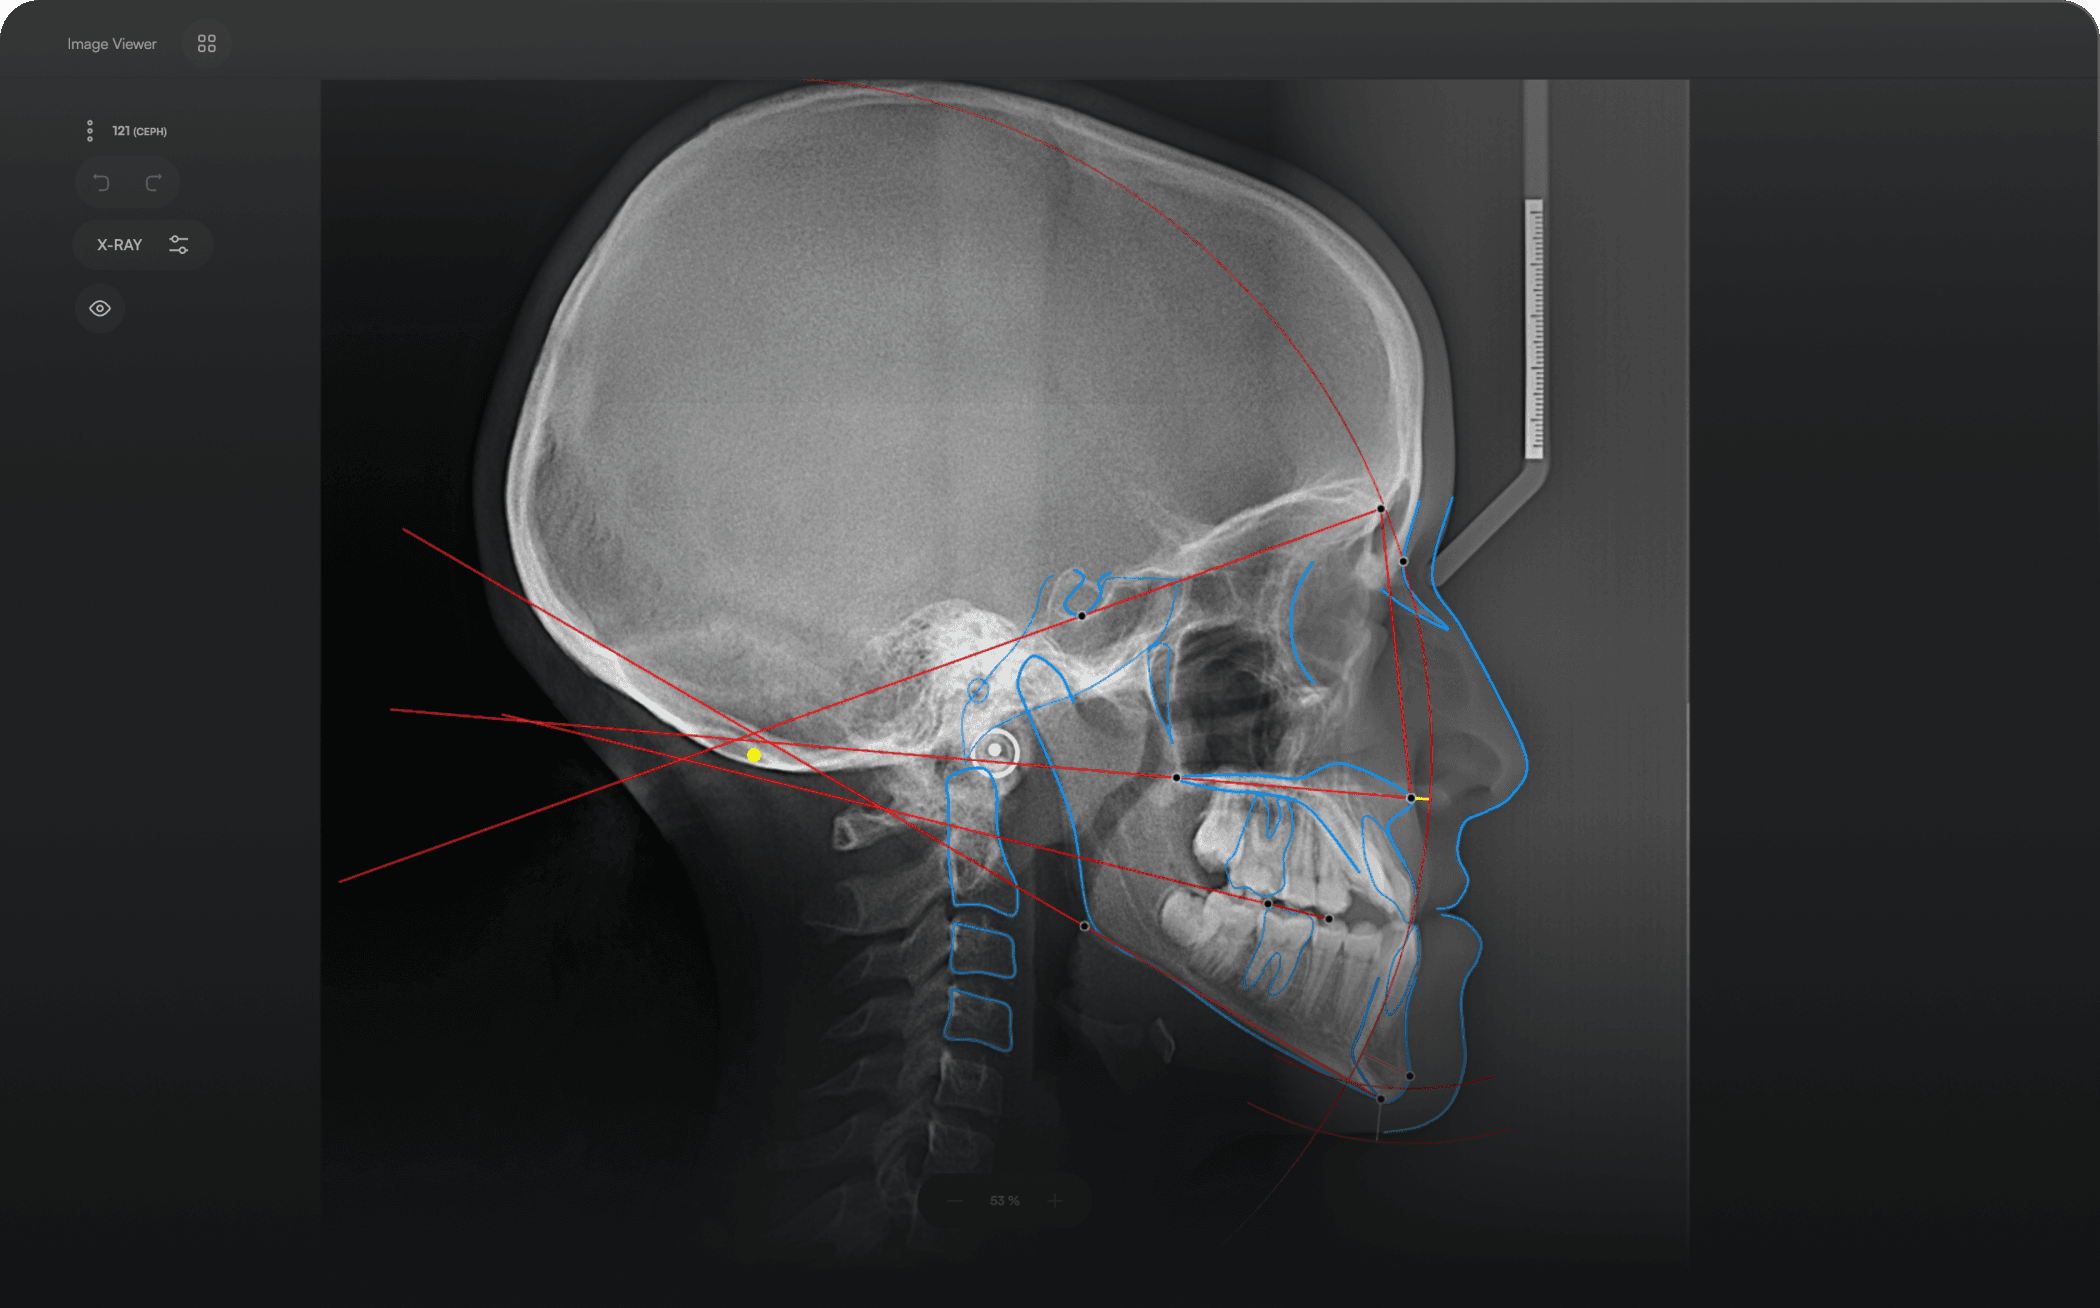

AI-driven Automated Lateral

Cephalometric Tracing

150+ landmarks traced in seconds

Automated analyses

Identify 150+ orthodontic landmarks in under 10 seconds — a task that

traditionally may take more than 30 minutes.

Access automated studies like Steiner and Jefferson to assist in clinical assessment and enhance case evaluations.

Experience a comprehensive assessment of skeletal, dental, and soft tissue discrepancies.